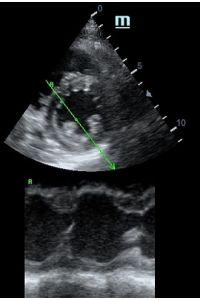

Оценка кооптации нижней полой вены ещё никогда не была такой простой и точной, никаких лишних деталей, просто устанавливаем клипер по анэхогенному участку.